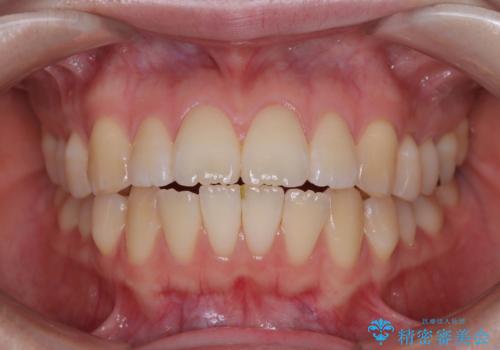

飛び出した前歯を引っ込める ワイヤー装置での抜歯矯正治療

- くちばしのように飛び出した前歯を気にして来院された患者様です。

上下左右の第一小臼歯4本を抜歯して、ワイヤー装置にて矯正治療を行うこととしました。

舌の突出癖により、口元が突出しているだけでなく、上下前歯が非接触となっておりました。

舌のトレーニングをしっかりと行っていただくことで、2年を切って治療を終えるとともに

、上下前歯を接触させることができました。